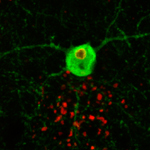

EL és una forma progressiva i hereditària d'epilèpsia que provoca una neurodegeneració irreversible per a la qual no existeix cura o tractament efectiu en l'actualitat. La malaltia sol manifestar-se durant les últimes etapes de la infantesa o l'adolescència, generalment en forma de crisis epilèptiques que més endavant desemboquen en el deteriorament irreversible de les funcions neurològiques. Una de les característiques de la malaltia és l'acumulació anormal d'agregats de glucogen, coneguts com cossos de Lafora (CL), en les neurones. En aquestes cèl·lules, dos gens, malina i laforina, actuen conjuntament per bloquejar l'acumulació de glicogen en condicions normals. Mutacions-canvis en el DNA-en qualsevol d'aquests dos gens són responsables de la malaltia.

A més "l’estudi evidencia l’existència de CL en un tipus especial de cèl·lules del cervell conegudes com interneurones inhibitòries". Dins la complexa arquitectura del cervell aquestes cèl·lules s'encarreguen de generar 'senyals de parada' per excitació neuronal. Els investigadors proposen que la major excitabilitat de les neurones i la propensió a les crisis epilèptiques que s'observen en aquests ratolins genèticament modificats estan relacionats amb la pèrdua d’interneurones inhibitòries. Resulta interessant a més que altres tipus d'epilèpsia, esquizofrènia i altres malalties neurodegeneratives com l'Alzheimer, es caracteritzen també per la pèrdua d'aquest tipus de cèl·lules cerebrals.